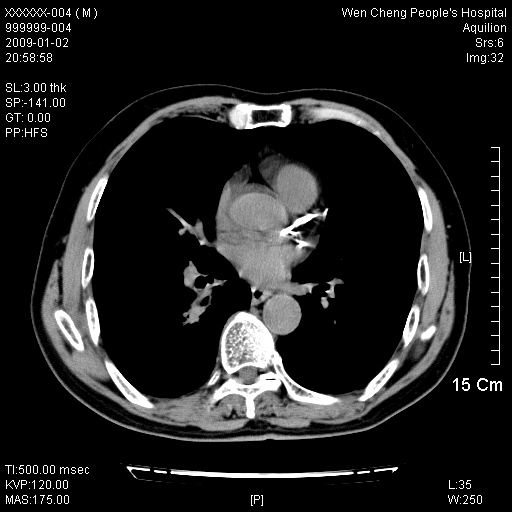

男性,73岁,有慢支病史,肿瘤系列标志物检验正常,血沉及血常规正常

右肺下叶背段小片状 磨玻璃样模糊影,内见血管及含气支气管像,支气管管壁增厚。考虑:慢性炎症!

右肺下叶背段小片状 实性与磨玻璃样影,内见血管及含气支气管像,支气管管壁增厚,边缘见长毛刺影。考虑:慢性炎症或肿瘤!建议抗炎治疗复查,密切观察随访!

右肺下叶片团状影内见扩张的含气支气管和支气管管壁增厚,其周有磨玻璃样模糊影和长毛刺。考虑慢性炎症可能性大。

2、右肺下叶片团状影内见扩张的含气支气管和支气管管壁增厚,其周有磨玻璃样模糊影和长毛刺。考虑周围型肺ca可能,结核不排。

高度提示细支气管肺泡癌,建议抗炎治疗半月观察病灶变化,如无明显改变,建议立即手术治疗.

病变形态非常不好呀,临床上血常规及症状也不明显,不太支持炎性病灶,高度警惕肿瘤病变,最好做个纤支镜检查。